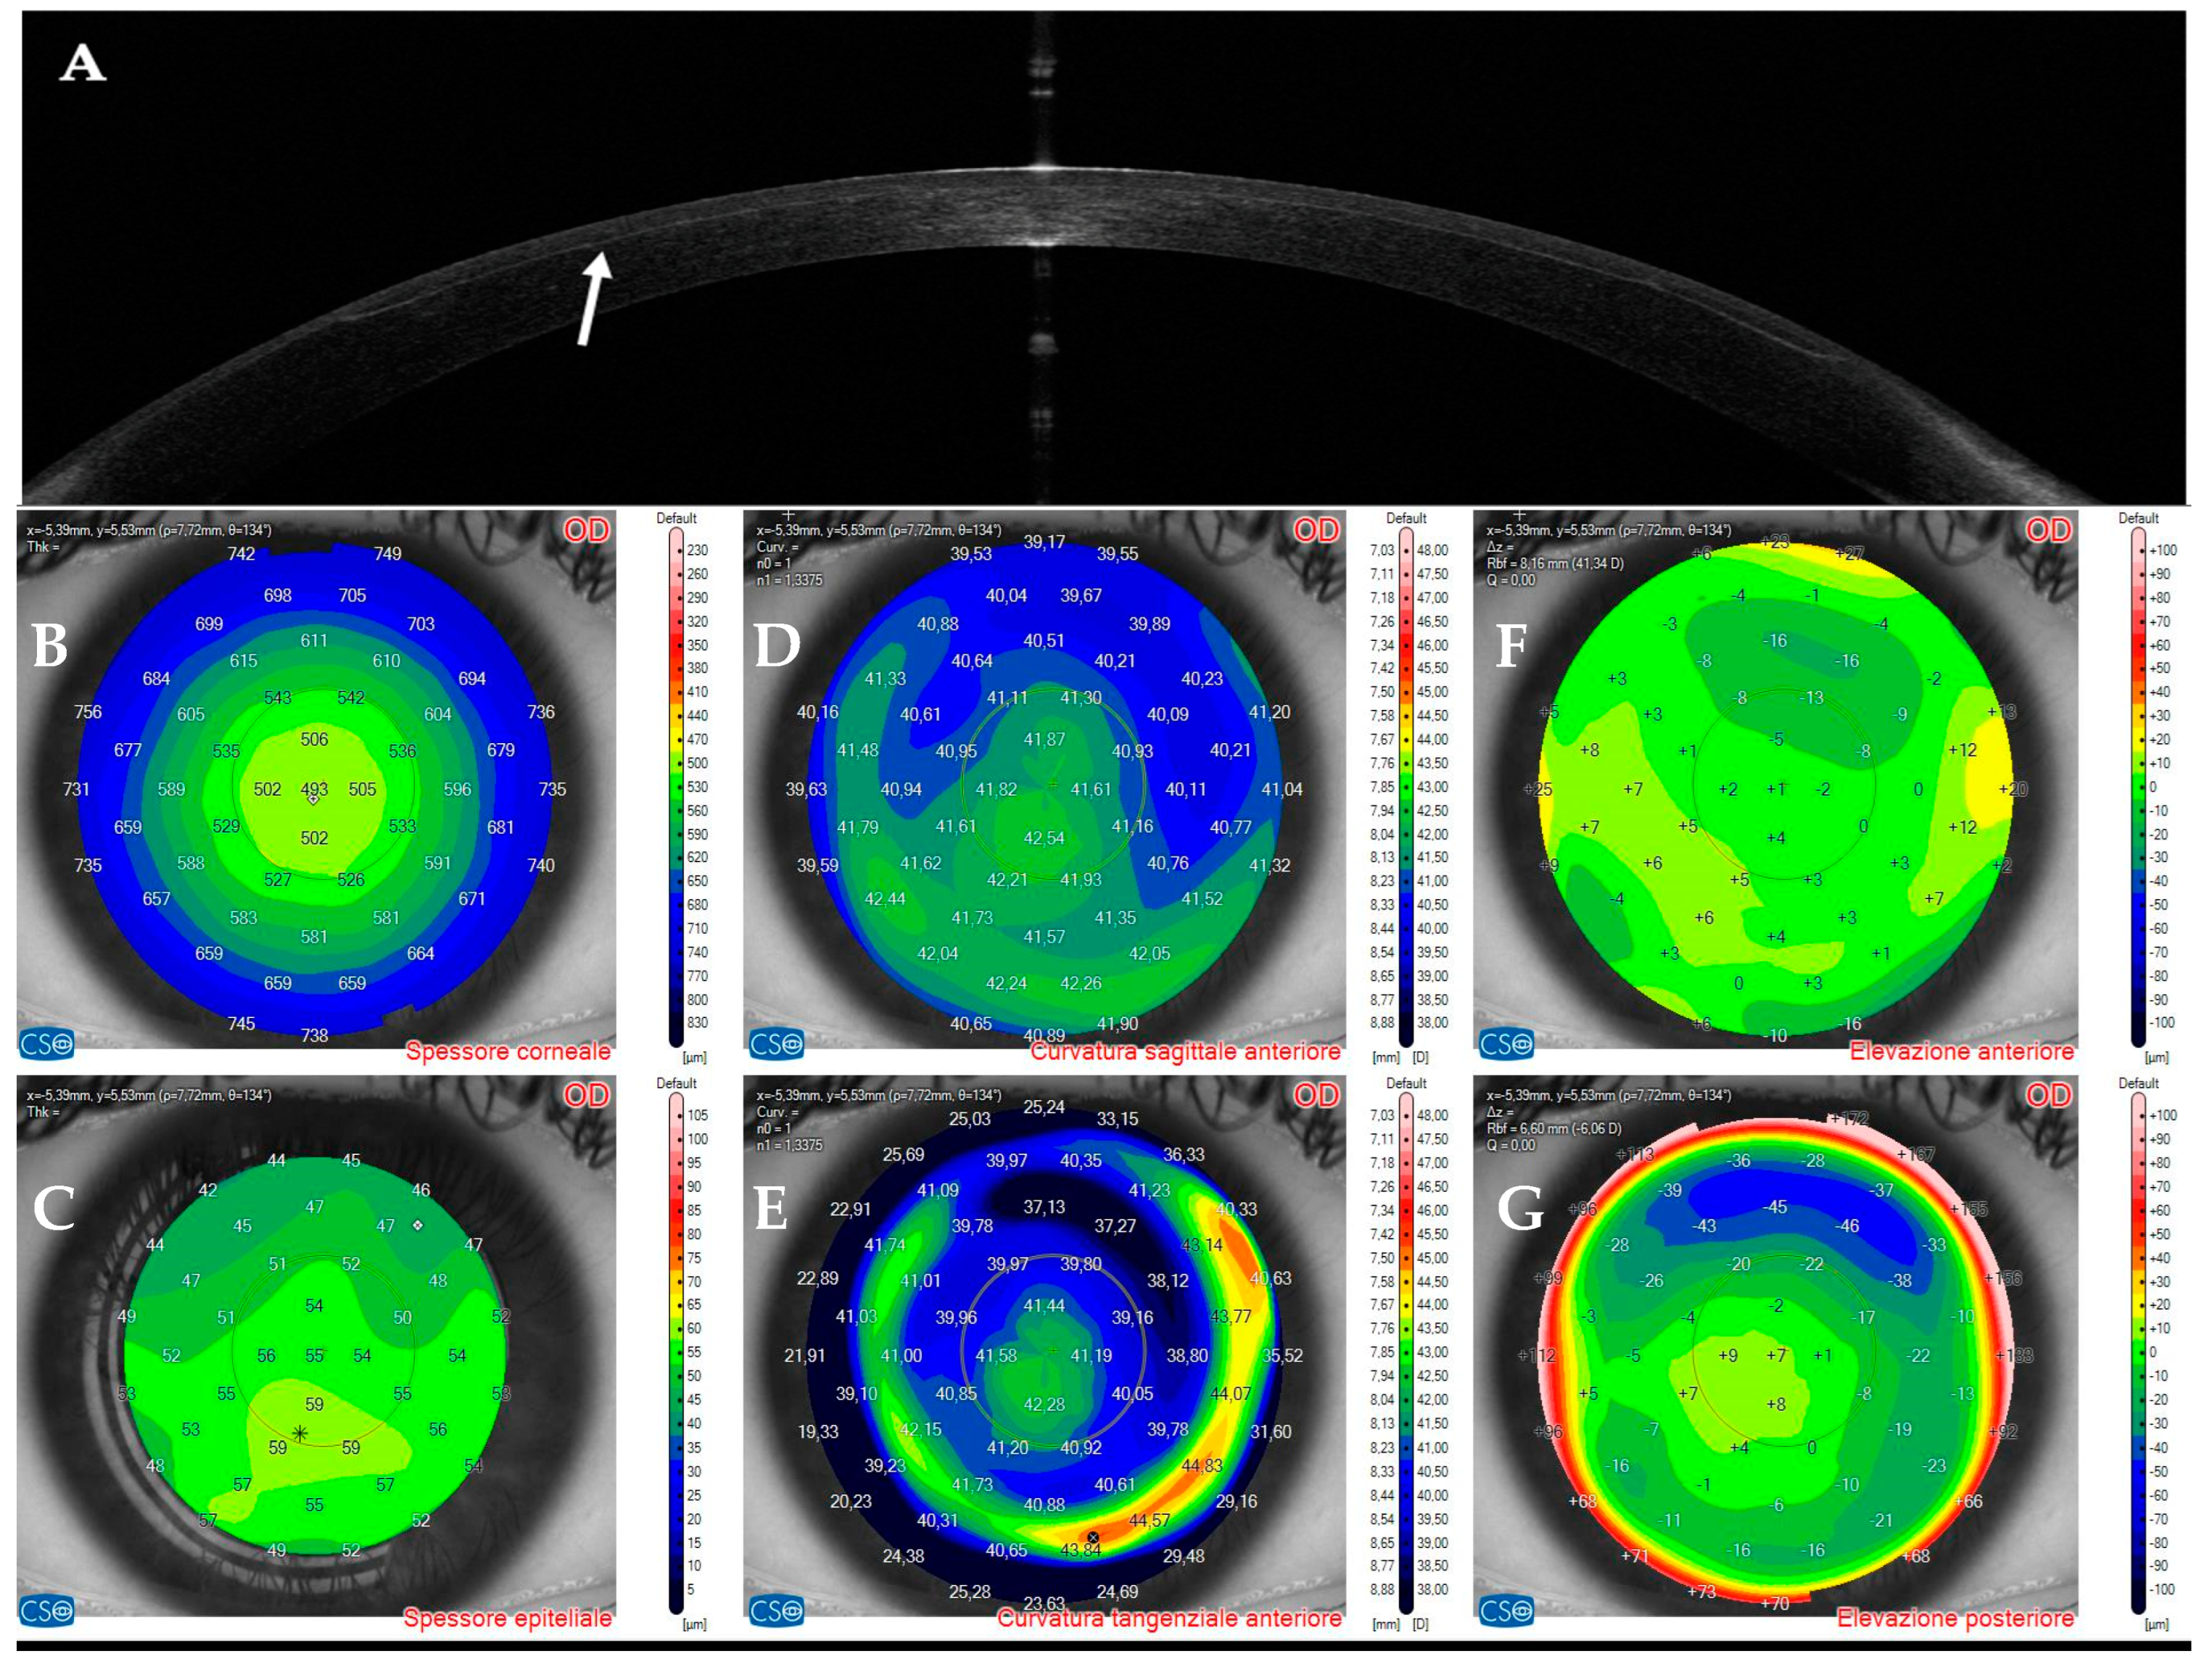

3.1. Patient #1